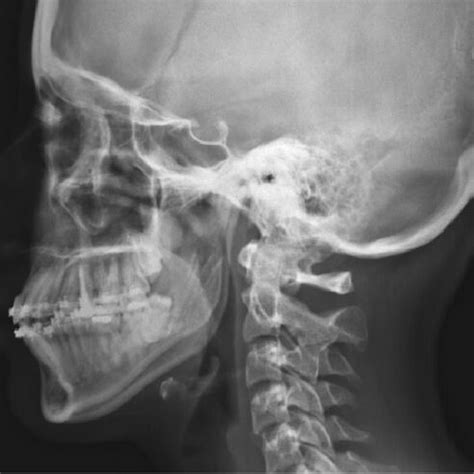

- Pruebas de imagen: Para afinar el diagnóstico, casi siempre usamos alguna imagen. La ecografía (ultrasonido) del área submandibular es muy útil: es rápida, indolora y nos dice si el bulto es sólido o lleno de líquido, su tamaño exacto y características internas. Con una eco podemos distinguir bastante bien un ganglio linfático (tiene cierta forma y ecotextura característica) de un quiste (lesión líquida) o de un tumor sólido. Si persiste duda, pasamos a estudios más detallados: una radiografía panorámica dental detectará si hay lesiones óseas o abscesos dentales ocultos; una Tomografía Computarizada (TAC) o Resonancia Magnética (RMN) nos dará una imagen más precisa de la ubicación del bulto, su relación con estructuras vecinas y sospecha de naturaleza. Por ejemplo, ante un quiste mandibular grande, el TAC mostrará la cavidad en el hueso; ante un tumor de glándula, la RMN delineará sus bordes y extensión.